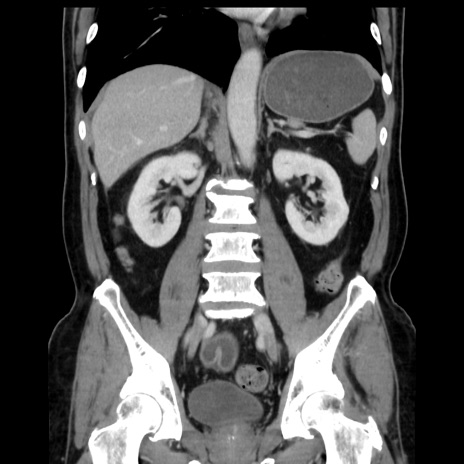

症例16(冠状断像)

【症例】 70歳代男性

【主訴】 腹痛、嘔吐

【現病歴】 約1ヶ月前より間欠的に腹痛と嘔吐あり、当院消化器内科を受診したところCTで多発する肝臓のLDAを指摘され、精査中であった。以降は消化器症状は安定していたが、2日前より嘔気と腹痛があり、同日より排便・排ガスが消失した。改善認めず、 本日、救急外来を受診した。

【既往歴】 大腸ポリープ切除後。

【身体所見】意識清明・会話良好、BT 36.3℃、BP 127/80mmHg、 P 80bpm、腹部:膨満あり、平坦・軟、上腹部正中および下腹部正中に圧痛あり、反跳痛なし、筋性防御なし。

【データ】WBC 7200、CRP 0.77